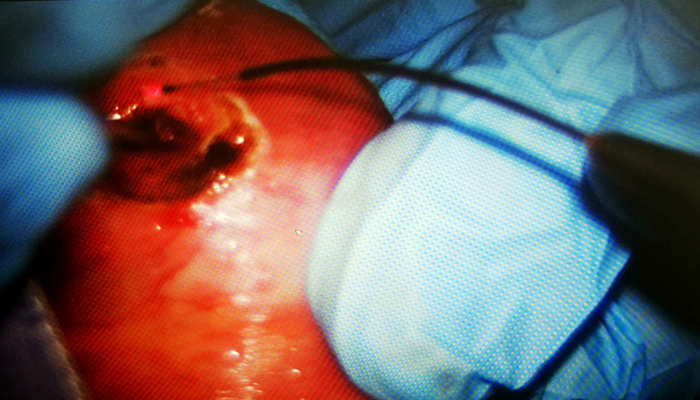

近日,北京佑安医院口腔科在陈世璋主任的指导下,成功的为一名患者应用激光显微技术实施了口腔肿物切除手术。这是北京佑安医院口腔科新开展的激光及显微颌面部手术治疗技术,取得了良好的临床效果,此类治疗技术也是目前国际和国内推崇的微创精准化治疗方式。

激光手术除了具有增强局部抗感染能力、增强细胞代谢和酶活性,止血准确及时,加速创面愈合等优点外,其产生的瞬间热效应,可破坏神经末梢,抑制传导神经冲动,具良好的抗炎及镇痛效果。不仅大大地降低了并发症的发生也明显减轻了患者术后的痛苦其与微创技术结合更可达到高精度、小创伤等优点,尤其在面部肿物的切除术中可最大限度保存正常组织,减轻瘢痕及畸形。 微创治疗技术的开展为今后科室整体的精准治疗起到了很好的推进作用,也将极大的促进口腔科教学和科研工作的发展。